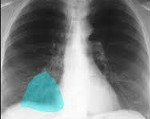

Q33.1 Добавочная доля легкого